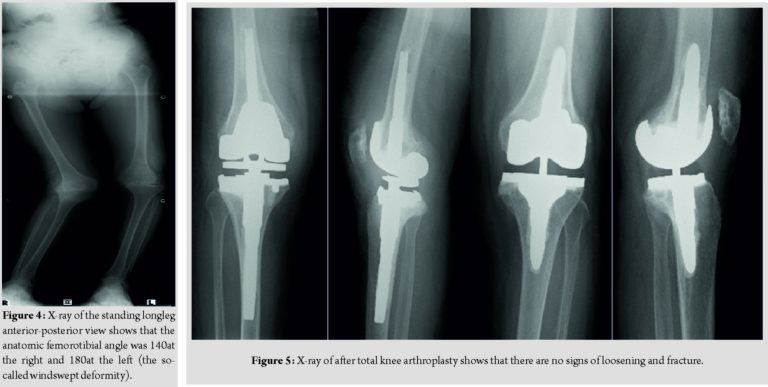

She demonstrated right drop foot immediately after the first operation. We prescribed an ankle–foot orthosis for her right ankle and started her rehabilitation therapy. The muscle power of her tibialis anterior slowly improved (MMT 3) over 3 months postoperatively. The active range of motion of the right knee was 5–95. However, the patient was unable to walk because of the left knee instability. We decided to then perform TKA for the left knee. We selected a constrained condylar prosthesis (Triathlon TS; Stryker, Mahwah, NJ, USA) using the same approach as in the first surgery. Intraoperatively, we removed a large loose body that was found in the suprapatellar pouch and performed a lateral retinaculum release and patella replacement. The active range of motion of the left knee was 0–95 and the patellar tracking was good. At the time of the 6-month follow-up, both knees were stable and in good alignment. There were no signs of loosening or fracture (Fig. 5). The patient experienced no pain and was able to ambulate throughout her house with a walker.